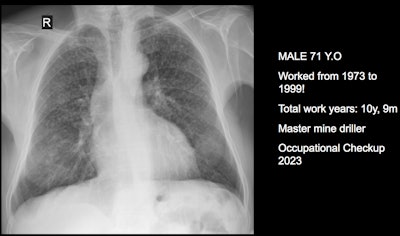

Three clinical cases courtesy of Luis Antonio Campos Calderon, MD.

The International Labor Organization (ILO) International Classification of Radiographs of Pneumoconioses is used for epidemiological studies, screening, and surveillance of workers exposed to dust in the workplace, and clinical purposes, and the National Institute for Occupational Safety and Health (NIOSH) B Reader Program certifies physicians in the ILO classification system. Each case should discuss its ILO classification and brief comments about the workflow, Campos Calderon noted.

The main diagnostic criteria are: Work history (minimum 10 years exposure to silica dust or other particles); chest x-ray (micronodular pulmonary fibrosis, coded according to ILO classification); progression (image profusion increases over time, even after exposure cessation; irreversibility (disease is progressive and irreversible, no stable pneumoconiosis over time).